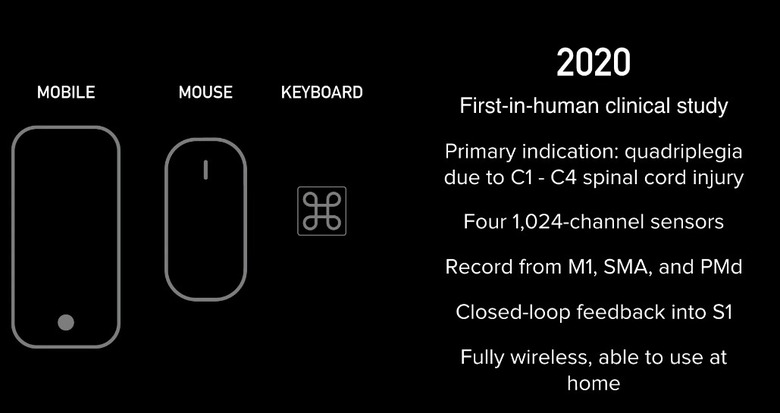

One big reveal is that it "hopes" to begin working on human subjects as soon as the second quarter of next year. In the picture above, that was shown during the presentation, that small protrusion at the bottom right with the arrow pointing to it, is the size of the thread that it actually hopes to implant.

According to Musk, its current v1 4x4mm chip is capable of 10,000 electrodes with "read and write" capability, which he says is more than 1,000 times the number of the best deep brain interface currently available for Parkinson's treatment.